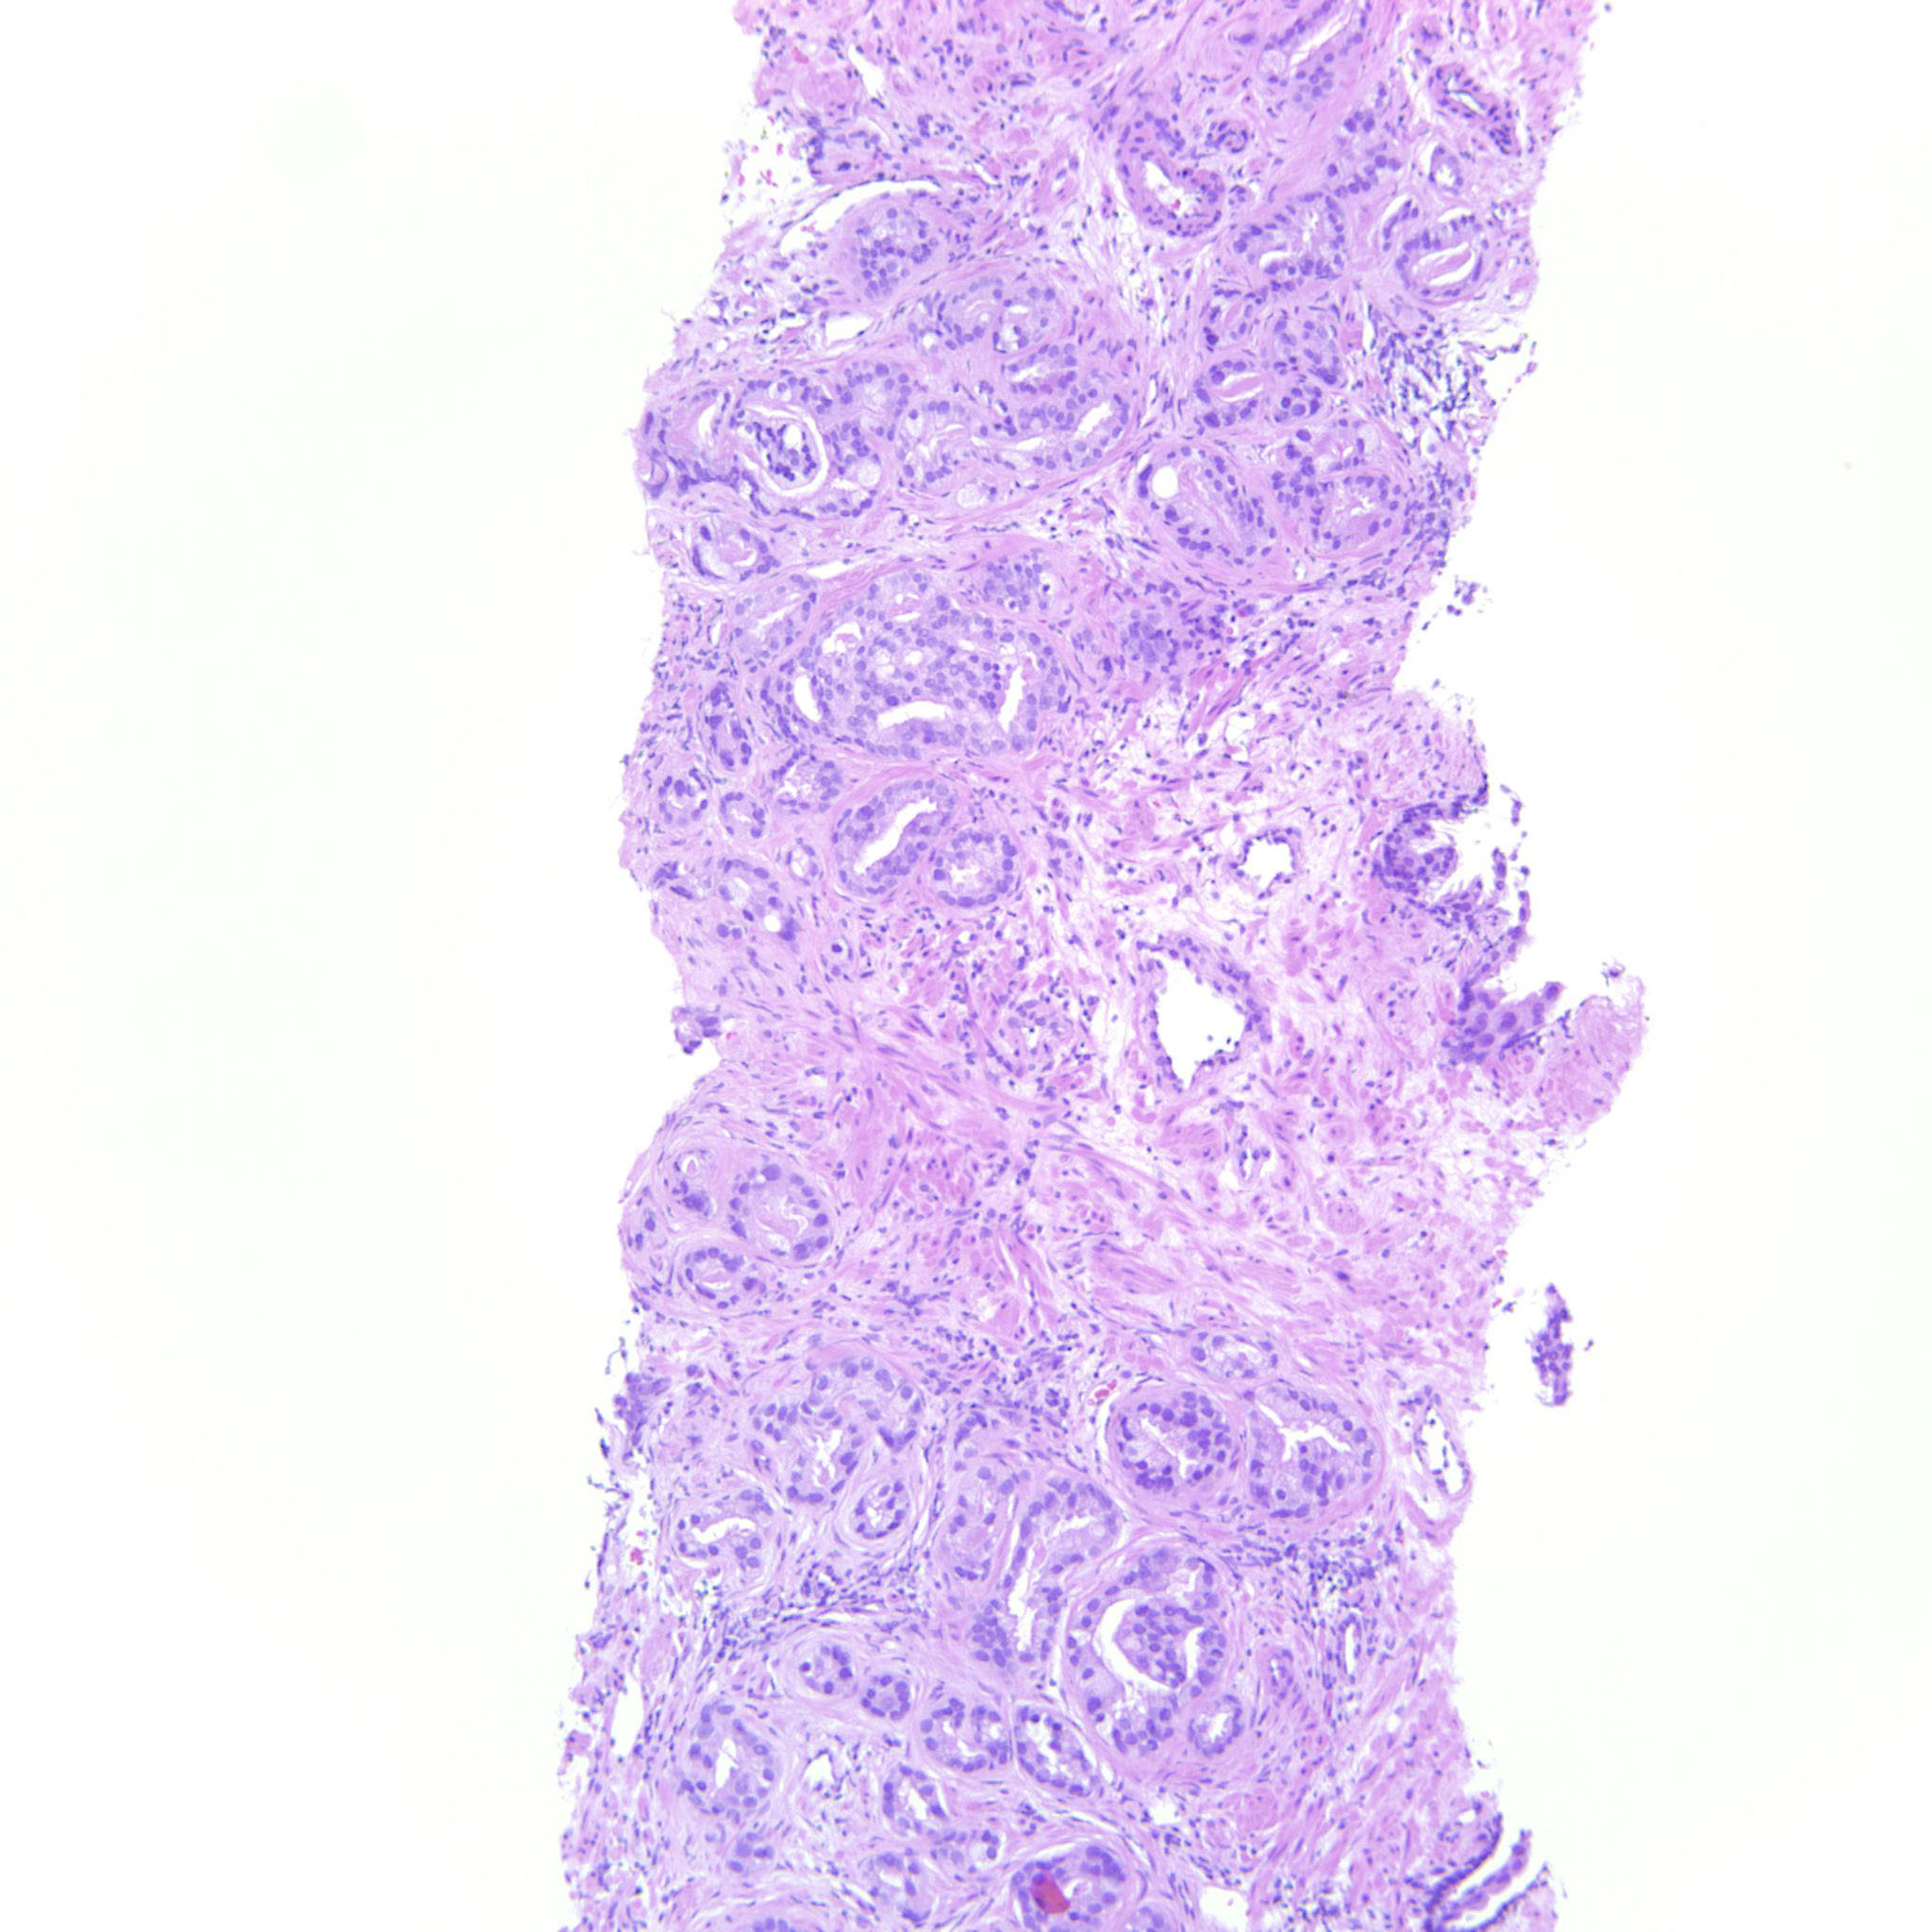

Prostate cancer grading

Case ID: 146